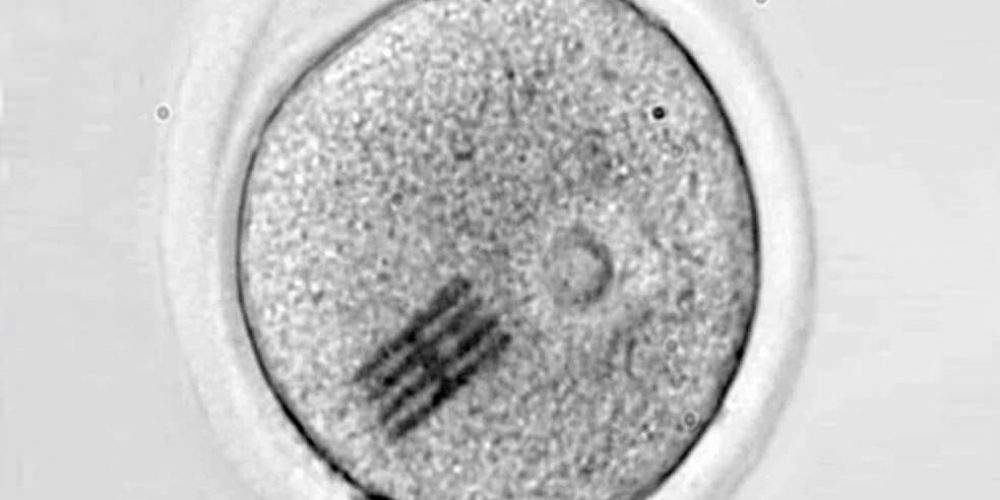

El chip funciona como sensor mecánico y es extremadamente minúsculo: mide apenas 22 por 10,5 micrometros, con 25 nanometros de grosor. Esto significa que tiene una longitud tres veces más pequeña que el diámetro de un cabello humano, y un espesor tres veces menor que el de un virus como el SARS-CoV-2.

Los dispositivos se han fabricado en la sala blanca del IMB-CNM bajo la supervisión del científico José Antonio Plaza. Luego, en un laboratorio de la Universidad de Bath, otro equipo dirigido por Anthony C. F. Perry ha inyectado el chip junto con un espermatozoide en el interior de un óvulo de ratón para analizar las etapas tempranas de la fertilización. Este proceso inicial ocurre de forma similar en los humanos.

Con el dispositivo dentro, han podido medir las fuerzas que reorganizan el interior del óvulo, es decir, su citoplasma, desde que se introduce el espermatozoide hasta que se divide en dos células.

“Haciendo un símil con el baile, el embrión realiza una coreografía de movimientos durante su desarrollo y hemos visto que no sólo el movimiento es importante sino también la intensidad del mismo”, comenta Plaza, “y a través de microscopia, podemos ver cómo el chip se dobla en el interior de la célula”.

“Dado que hemos modelizado y conocemos perfectamente qué fuerza hay que aplicar para que se doble el chip de una determinada manera –añade–, visualizando la curvatura podemos inferir qué fuerzas mecánicas se están dando en el interior celular”.